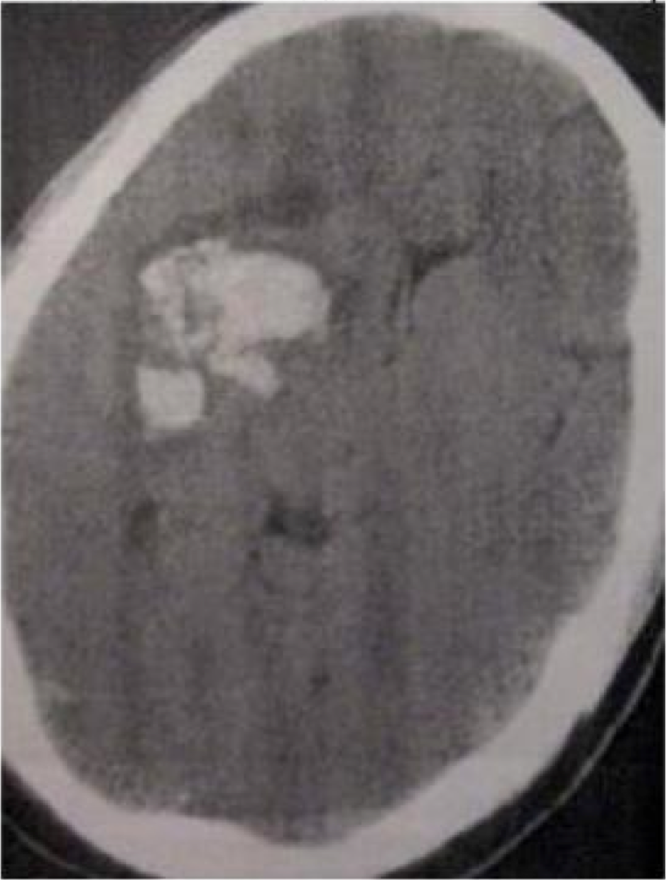

T. X, 58 tahun datang dengan sakit kepala hebat dan hemiparesis sebelah kiri. diagnosisnya adalah….

A. Perdarahan Hipertensif

B. Aneurisma Arteri serebral tengah yang pecah

C. Angiopati amilid

D. Vaskulitis

E. Malformasi venus-arterial yang pecah

A